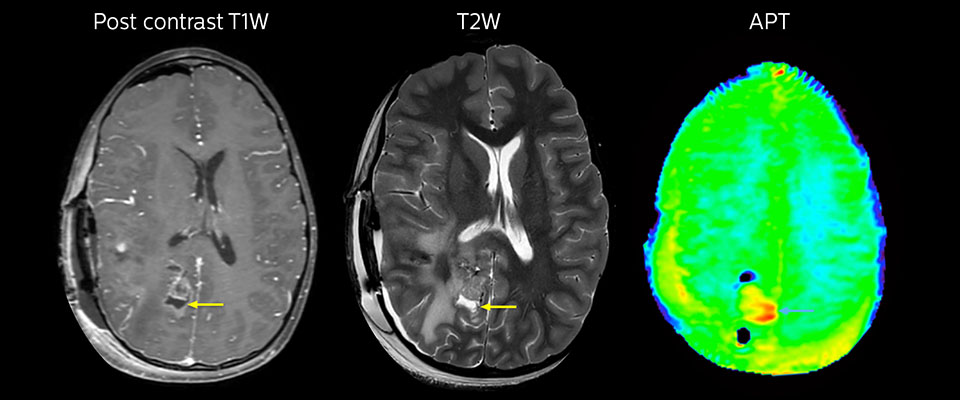

MRI with APT post resection

Immediately post resection MRI was again performed. T2-weighted and postcontrast T1-weighted images are quite inconclusive for distinguishing residual tumor tissue from postoperative tissue changes. On the APT image some high signal is still seen, which would suggest residual tumor tissue.

Follow-up over time

In later follow-up scans the post-contrast T1-weighted images suggest recurrent tumor growth. So, it would be interesting to study the predictive value of APT in a large patient group.

MRI may be performed after tumor resection, to look for residual tumor or tumor regrowth. Also here, the different contrast mechanism of APT may help in diagnosis. Dr. Miller remembers a particular case. “After a very good resection, we saw small changes on the postcontrast T1-weighted and the T2-weighted images that looked like a post-surgical little bit of fluid. Interestingly, however, we saw a focal area of APT signal, right in the center of that abnormality. As we usually do when a bit unsure, we followed it up and, unfortunately, found tumor regrowth in that region,” Dr. Miller says. “Cases like this motivate me, and others who care about this population, to investigate how this APT method could be used on large scale in this population and help us in providing high value diagnostic information.” The hospital’s physicians also saw a case where APT had a negative predictive value. Following the resection of a highgrade tumor, they saw a similar small change in the images of this patient. However in this case, the APT signal was rather low. In a recent rescanning of this patient, no recurrence was seen.